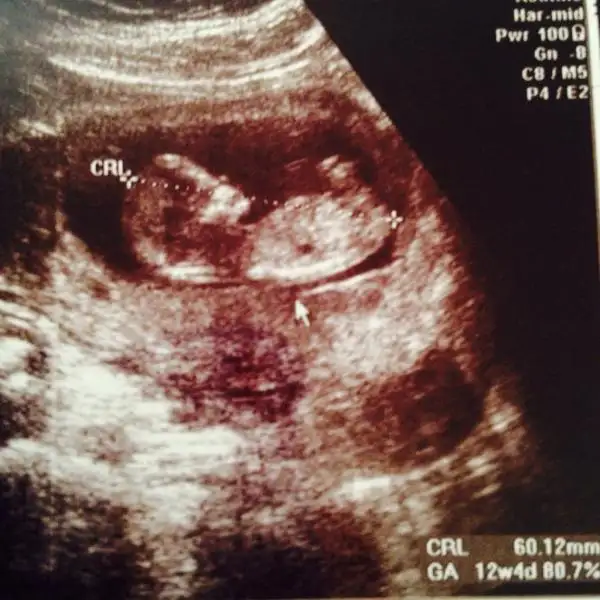

Aslında daha önce sormuştum ama tek bir arkadaş yorum yazdı belki farklı görüşler olur diye tekrar fikir almak istedim :) burda 12+1 iz normalde ama 3 gün önden gidiyoruz 12+4 görünüyor o yüzden minnağım :)

Eki Görüntüle 1214628 %90 kız dedi bir hekim diğer başka hekim birşey söyleyemedi

eger o çıkıntı ayak değilse erkek gibi duruyorKIZLAR SİZCE BENİMKİ NE